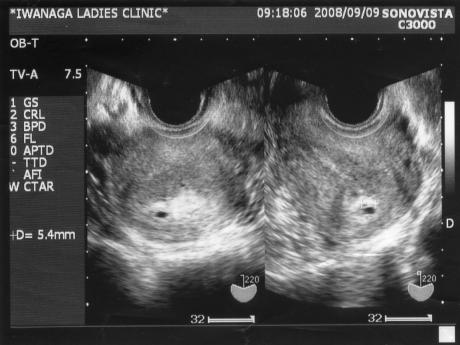

妊娠2ヶ月 妊娠4週 5週 6週 7週 妊娠初期 の超音波写真 妊娠 出産 育児に関する総合情報サイト ベビカム

妊娠4週目 4w0d 6d のエコー写真とエピソード 妊娠2ヶ月 Cozre コズレ 子育てマガジン

胎嚢の大きさの平均ってどれくらいなの ママリ

妊娠4週0日 4w0d の超音波 エコー 写真

エコー画像 マメちゃん4週目 キューティーベリー 楽天ブログ

妊娠4週4日 エコー写真 私と赤ちゃんと時々し ちゃん

2007 3 16 4週5日 スヌーピーの日記

妊娠4週6日目 初めての検診 たまちゃんといっしょ

4週5日目 病院で妊娠を確認 妊娠と出産と それから

妊娠2ヶ月 妊娠4週 5週 6週 7週 妊娠初期 の超音波写真 妊娠 出産 育児に関する総合情報サイト ベビカム

妊娠4週 3 6日 のエコー写真 体験談

妊娠4週5日目 超音波写真 Paparinko S Diary

5 産科一般超音波検査 初期編 正常所見4 7週 日本産婦人科医会

妊娠4週3日 4w3d の超音波 エコー 写真

妊娠4週4日 4w4d の超音波 エコー 写真

妊娠4週 赤ちゃんのエコー写真 超音波写真まとめ たまひよ